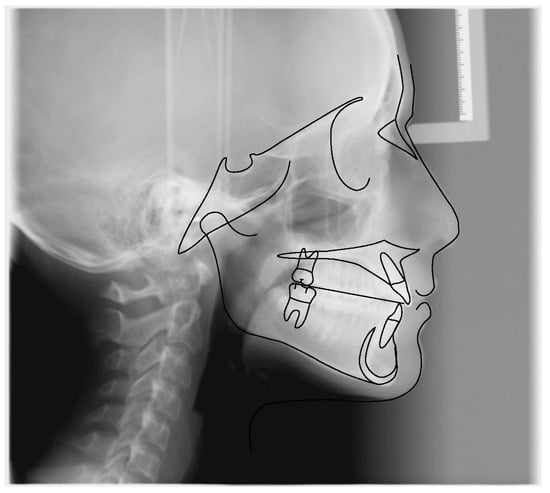

3.2. Clinical Case #2

| Cephalometric Analysis before Treatment | Val | Dev | Min | Med | Max | Diff |

|---|---|---|---|---|---|---|

| SNA | 82.4° | N | 80° | 82° | 84° | 0° |

| SNB | 83.2° | x | 78° | 80° | 82° | 1.2° |

| ANB | −0.8° | −x | 0° | 2° | 4° | 0.8° |

| sna-snp^Go-Gn | 22.4° | N | 15° | 20° | 25° | 0° |

| S-N^sna-snp | 7.6° | N | 7° | 10° | 13° | 0° |

| S-N^PO | 20.4° | xx | 11° | 14° | 17° | 3.4° |

| S-N^Go-Gn | 30° | N | 27° | 32° | 37° | 0° |

| SNBa | 134.5° | x | 124° | 129° | 134° | 0.5° |

| SND | 78.8° | x | 74° | 76° | 78° | 0.8° |

| IS^II | 142.5° | xx | 125° | 130° | 135° | 7.5° |

| IS:N-A | 2.2 | −x | 3 | 4 | 5 | 0.8 |

| II:N-B | 3.2 | N | 3 | 4 | 5 | 0 |

| II:A-Pog | 2.9 | N | −1 | 1 | 3 | 0 |

| Ls:Line S | −1.6 | −x | −1 | 0 | 1 | 0.6 |

| Li: Line S | −1.4 | −x | −1 | 0 | 1 | 0.4 |

| Cvm:S-Gn | 1 | N | −1 | 0 | 1 | 0 |

| Mol Sup^P. Occl | 106° | xxx | 88° | 90° | 92° | 14° |

| N-S-Cop | 134.1° | xx | 117° | 122° | 127° | 7.1° |

| S-Cop-Go | 132.8° | −x | 137° | 143° | 149° | 4.2° |

| Cop-Go-Gn | 123.1° | N | 115° | 120° | 125° | 0° |

| Cop-Go-N | 53.7° | x | 48° | 50° | 52° | 1.7° |

| N-Go-Gn | 69.3° | N | 68° | 70° | 72° | 0° |

| II^Go-Gn | 84.1° | −xxx | 92° | 93° | 94° | 7.9° |

| SOr:sna | 45 | 0 | 0 | 0 | 45 | |

| sna:Me | 51.2 | 0 | 0 | 0 | 51.2 | |

| S:N | 53.7 | −xxxxxx | 68.7 | 71.7 | 74.7 | 15 |

| snp:A | 40 | 0 | 0 | 0 | 40 | |

| Go:Me | 63.4 | −x | 66.7 | 71.7 | 76.7 | 3.3 |

| Wits | −8.5 | −xxxx | −2 | 0 | 2 | 6.5 |

| IS^N-S | 103.4° | x | 101° | 103° | 105° | 0° |

| Pog:N-B | 1.1 | 0 | 0 | 0 | 1.1 | |

| Pog:N-B—II:N-B | −2.1 | - | 0 | 0 | 0 | 2.1 |

| Cephalometric Analysis after Treatment | Val | Dev | Min | Med | Max | Diff |

| SNA | 84.6° | x | 80° | 82° | 84° | 0.6° |

| SNB | 84.2° | xx | 78° | 80° | 82° | 2.2° |

| ANB | 0.4° | N | 0° | 2° | 4° | 0° |

| sna-snp^Go-Gn | 20.1° | N | 15° | 20° | 25° | 0° |

| S-N^sna-snp | 11.6° | N | 7° | 10° | 13° | 0° |

| S-N^PO | 17.3° | x | 11° | 14° | 17° | 0.3° |

| S-N^Go-Gn | 31.7° | N | 27° | 32° | 37° | 0° |

| SNBa | 140.3° | xx | 124° | 129° | 134° | 6.3° |

| SND | 80.9° | xx | 74° | 76° | 78° | 2.9° |

| IS^II | 135.3° | x | 125° | 130° | 135° | 0.3° |

| IS:N-A | 2.7 | −x | 3 | 4 | 5 | 0.3 |

| II:N-B | 3.5 | N | 3 | 4 | 5 | 0 |

| II:A-Pog | 3.2 | x | −1 | 1 | 3 | 0.2 |

| Ls:Line S | −3.9 | −xxx | −1 | 0 | 1 | 2.9 |

| Li: Line S | −4.4 | −xxxx | −1 | 0 | 1 | 3.4 |

| Cvm:S-Gn | −3.6 | −xxx | −1 | 0 | 1 | 2.6 |

| Mol Sup^P. Occl | 108° | xxx | 88° | 90° | 92° | 16° |

| N-S-Cop | 137° | xxx | 117° | 122° | 127° | 10° |

| S-Cop-Go | 128.7° | −xx | 137° | 143° | 149° | 8.3° |

| Cop-Go-Gn | 126.1° | x | 115° | 120° | 125° | 1.1° |

| Cop-Go-N | 54.4° | xx | 48° | 50° | 52° | 2.4° |

| N-Go-Gn | 71.6° | N | 68° | 70° | 72° | 0° |

| II^Go-Gn | 79° | −xxx | 92° | 93° | 94° | 13° |

| SOr:sna | 63.3 | 0 | 0 | 0 | 63.3 | |

| sna:Me | 57.5 | 0 | 0 | 0 | 57.5 | |

| S:N | 59.4 | −xxxx | 68.7 | 71.7 | 74.7 | 9.3 |

| snp:A | 49.7 | 0 | 0 | 0 | 49.7 | |

| Go:Me | 74.6 | N | 66.7 | 71.7 | 76.7 | 0 |

| Wits | −7.8 | −xxx | −2 | 0 | 2 | 5.8 |

| IS^N-S | 113.9° | xxxxx | 101° | 103° | 105° | 8.9° |

| Pog:N-B | 0.3 | 0 | 0 | 0 | 0.3 | |

| Pog:N-B—II:N-B | −3.2 | - | 0 | 0 | 0 | 3.2 |